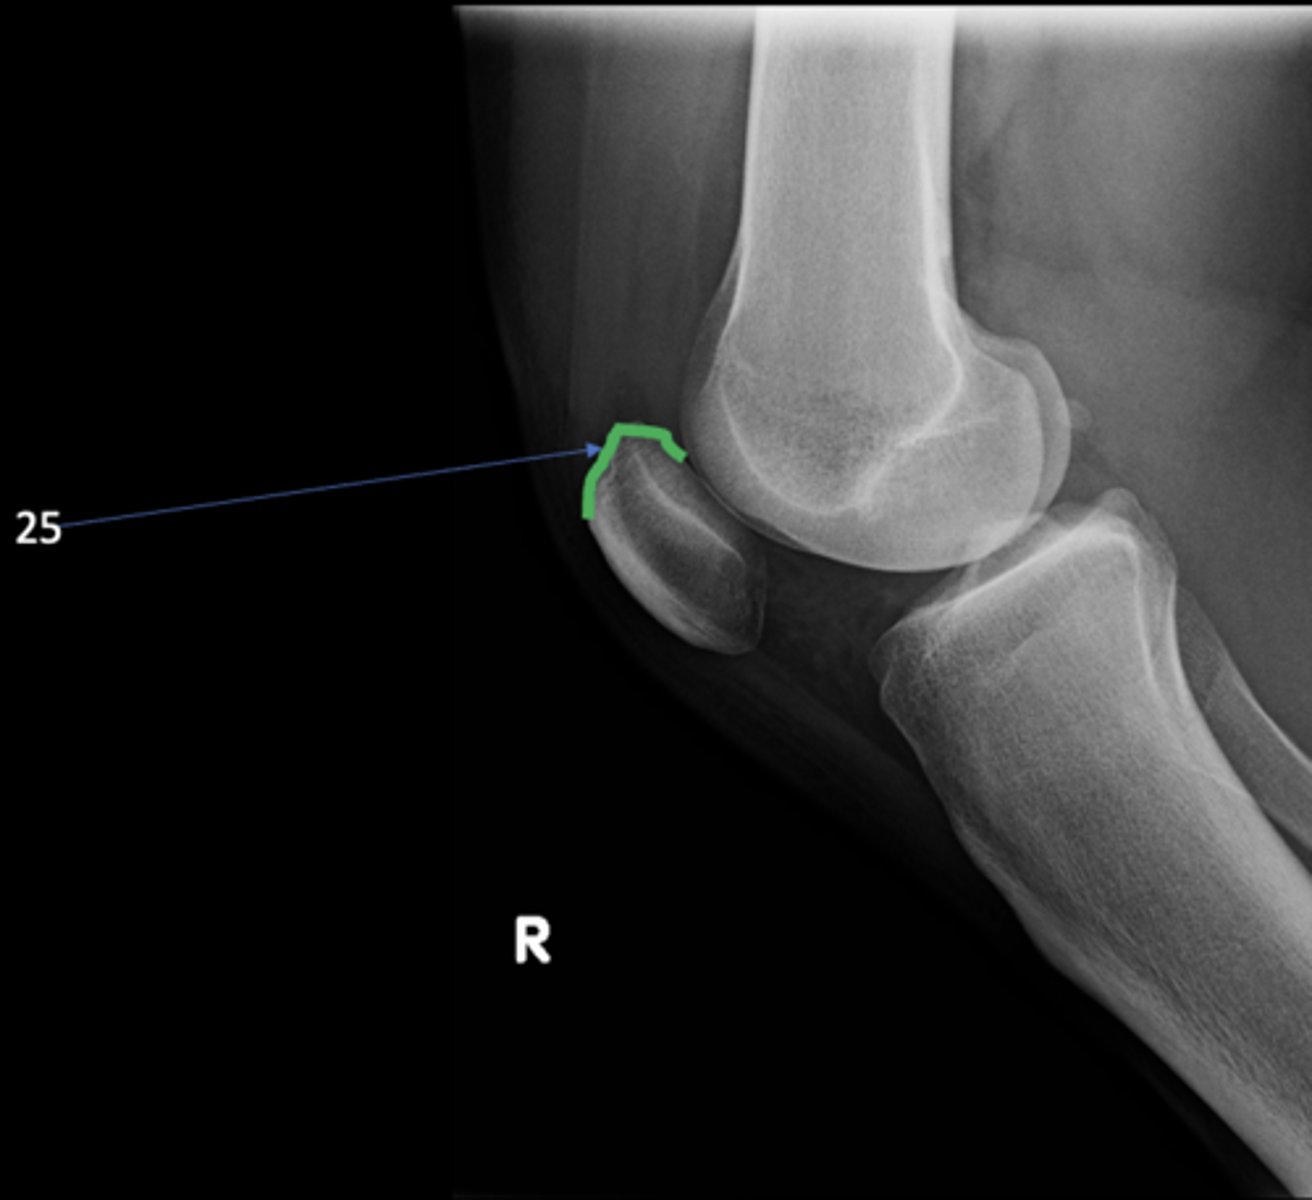

73

Superior aspect of patella

<p>ID 25</p>